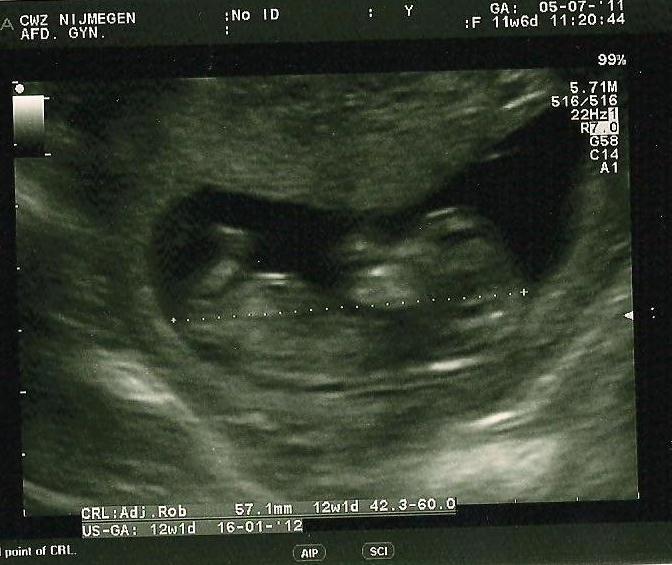

The scan is taken with 12 weeks: